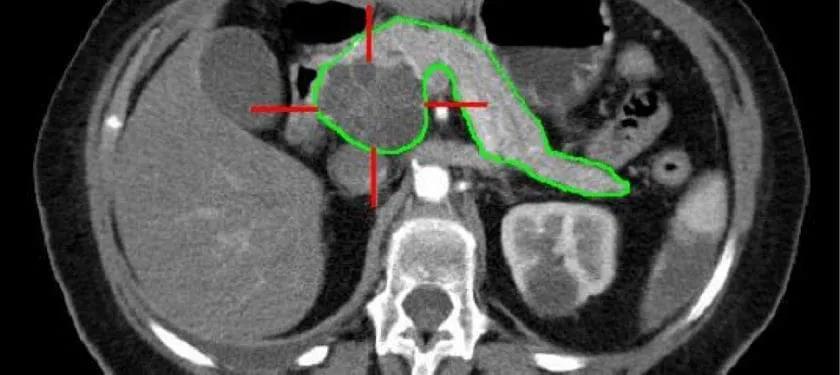

胰腺癌因其發(fā)病隱匿、發(fā)現(xiàn)晚、病情發(fā)展迅速、手術(shù)死亡率高、治愈率低等特點,被稱為“癌中之王”。近年來,其發(fā)病率和死亡率都在逐年上升。

然而,胰腺癌治療的進展,在患者預(yù)期壽命和生活質(zhì)量的改善上卻微乎其微。胰腺癌的存活率是所有常見癌癥中最低的,五年生存率只有7%,是預(yù)后最差的惡性腫瘤之一。

胰腺癌以侵襲性和難治性聞名,而且由于其位置的特殊性,使得癌細胞很容易擴散到鄰近的臟器,比如肝臟和胃。胰腺癌的特點,使得現(xiàn)有藥物很難進入腫瘤,并且胰腺癌免疫微環(huán)境比較特殊,免疫療法有效性也較低。而腎上腺髓質(zhì)素-2受體抑制劑有望讓胰腺癌患者獲益。